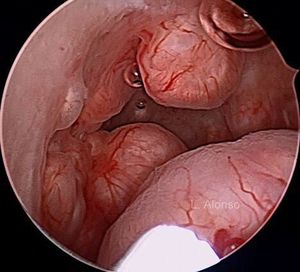

Hysteroscopy

Submucosal myomas are associated with abnormal uterine bleeding more than intramural and subserosal fibroids, presumably due to the distortion of the cavity and an increase in the bleeding surface of the endometrium